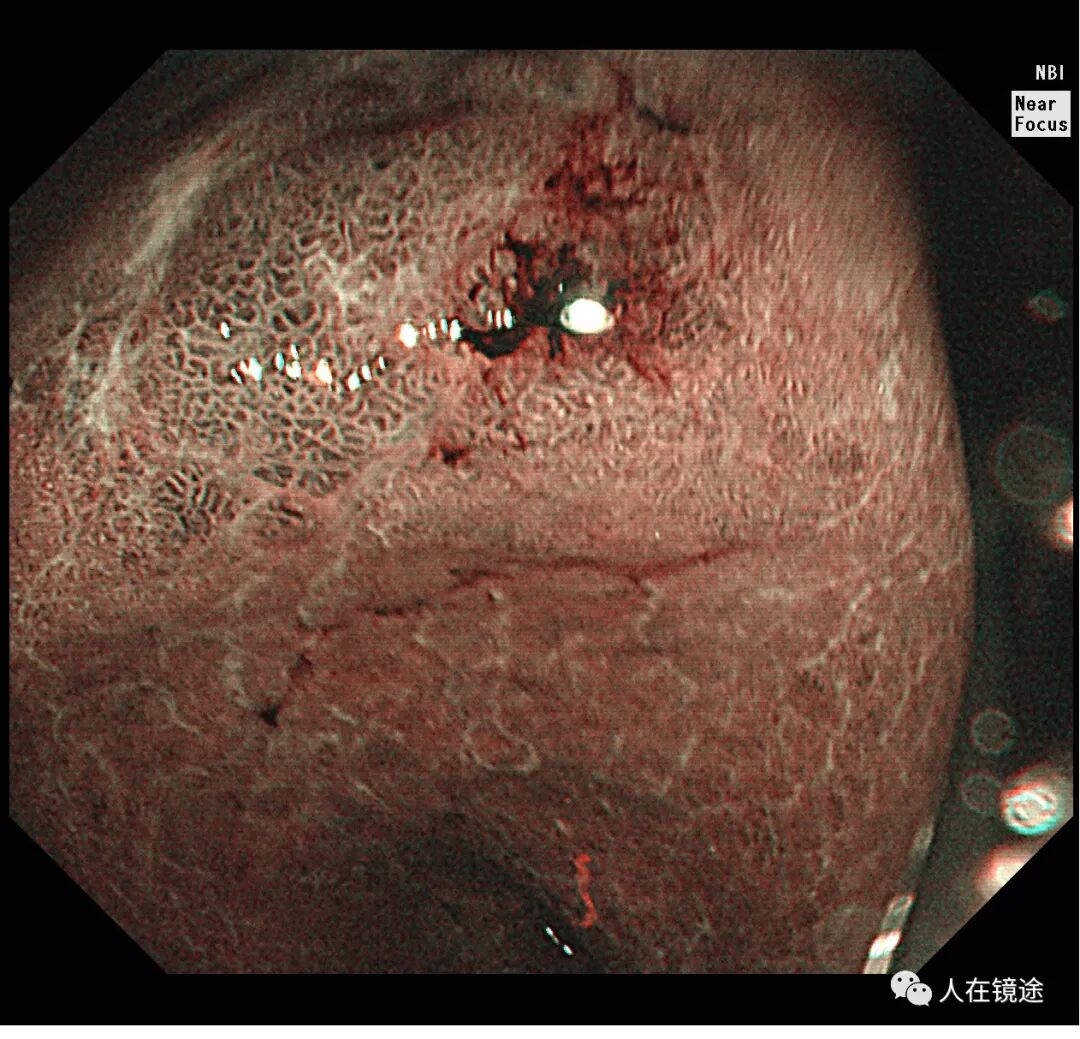

NBI+近焦示:胃窦小弯见一0.8*1.2cmIIa粘膜发病变呈咖色,边界清楚,微结构紊乱,表面粘膜高低不平伴自发性出血